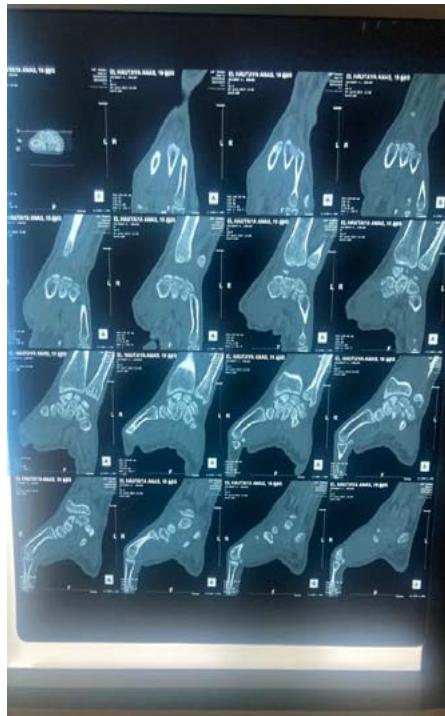

The standard radiographic assessment revealed a scaphoid fracture with an underlying gap, suggesting the possibility of a cyst or pseudarthrosis of the scaphoid (figure 1). The wrist CT scan confirmed the scaphoid fracture with a probable intraosseous cyst (figure 2).

Figure 2: The computed tomography (CT) scan confirmed the scaphoid fracture and the localized and nonaggressive nature of the cyst.